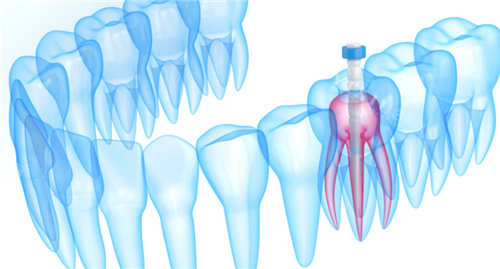

- 根管治疗:800-2000元/颗(前牙与后牙价格不同)